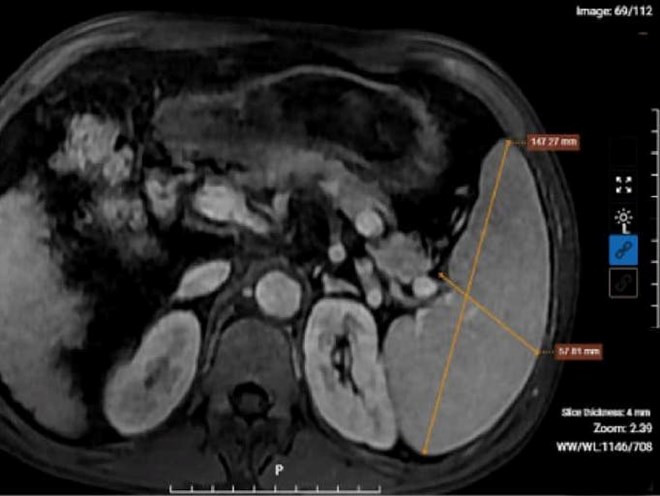

Kết quả chụp MRI của bệnh nhân nghiện rượu cho thấy hình ảnh xơ gan lách to, dịch bao quanh gan. (Ảnh: BVCC)

Sau khi thăm khám lâm sàng và thực hiện các xét nghiệm, chẩn đoán hình ảnh cần thiết, kết quả chỉ số men gan AST, ALT, Bilirubin trong máu của bệnh nhân tăng ở mức báo động, cùng tình trạng xơ gan mất bù, kèm theo dịch ổ bụng. Đồng thời, kết quả xét nghiệm của bệnh nhân còn phát hiện dương tính với viêm gan B. Bác sĩ đưa ra chẩn đoán xác định bệnh nhân mắc xơ gan mất bù kèm viêm gan B mạn tính.